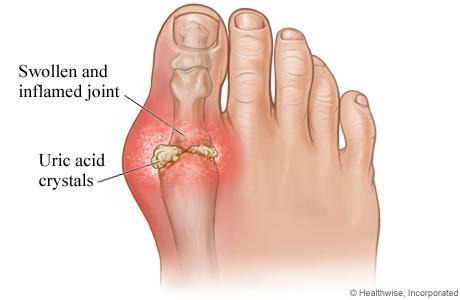

통풍

요산 결정이 관절에 쌓이면서 염증을 유발하는 질환입니다. 주로 엄지발가락 관절에 통증이 시작되지만, 발바닥 전체로 통증이 확산되기도 합니다. 심한 경우 붓기와 열감이 동반되어 신발 착용이 힘들 정도가 됩니다.